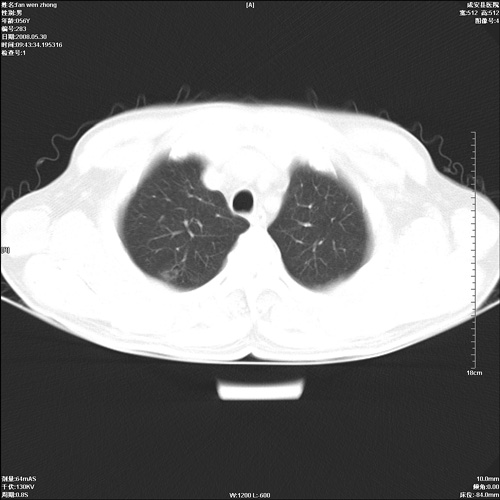

病人 男 56岁 一周前高热,体温达39-40度,经抗炎治疗后,体温渐降,达37,5-38度,轻微咳嗽,胸部不适 查白细胞为1.3万 行ct检查,请分析。

双肺内可见多发结节状病灶,并见小空洞,病人高热,白血球增高,应该是典型的迁徙性肺脓肿(多为金黄色葡萄球菌感染)。查一下口腔等其它部位有无感染灶。

双肺内可见多发结节状病灶,并见小空洞,病人高热,白血球增高,应该是典型的迁徙性肺脓肿(多为金黄色葡萄球菌感染)。建议治疗后复查.